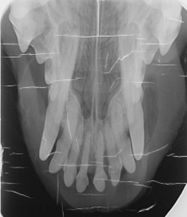

erityisen yleinen pienillä roduilla ja koskettaa näin merkittävästi myös havannankoiria. Tutkimusten mukaan vähintään 44 % koirista kärsii elämänsä aikana parodontiitista. Sairauden synty liittyy monitekijäisesti sekä koiran immuunijärjestelmän toimintaan että suun hoitoon. Tulehdus saa alkunsa hampaan pinnalle kertyvästä plakista, mutta parodontiitin etenemistä selittää usein poikkeava immuunireaktio tavalliseen ientulehdukseen. Myös perinnöllisellä alttiudella on osuutensa.

Miten tilanne voidaan todeta?

Parodontiitti voidaan varmuudella todeta vain hammasröntgenkuvauksessa. Tulehdus johtaa hampaiden kiinnityskudoksen heikentymiseen ja lopulta katoon, mikä saa hampaat löystymään. Pitkälle edennyt sairaus voi vaurioittaa myös leukaluuta. Suun tulehdukset kuormittavat lisäksi koko elimistöä, sillä ne voivat altistaa sisäelinten tulehduksille ja heikentää koiran vastustuskykyä.